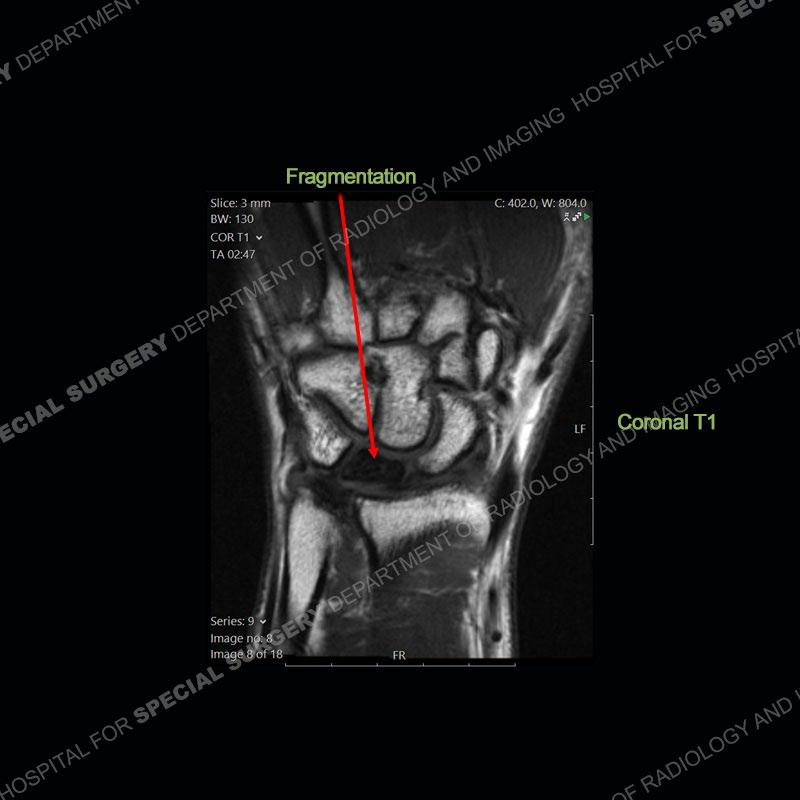

Both cases demonstrate similar findings to slightly less and more conspicuous degrees. The radiographs show sclerosis and fragmentation/collapse of the lunate. The CT images for case one just further clarify the architecture of the lunate. The MRI images show a slightly greater degree of variability but with overall persistent areas of low signal of the lunate on all pulse sequences and with a loss of the geometry of the lunate indicating collapse and fragmentation.

A well recognized but still poorly understood entity with necrosis and collapse representing the end stage of the pathology. The reasons for the necrosis are likely multifactorial and relate to the anatomy of the wrist inclusive of ulnar variance and the anatomy of the vasculature to the lunate. Other inflammatory, biological processes and overuse/trauma also likely play a role in the development of the necrosis. The disease manifests by sclerosis of the lunate followed by collapse and fragmentation. This is then followed by abnormal orientation of the scaphoid in a palmar flexed position and then adjacent arthritis. These latter processes were not the focus of this case presentation. The MRI will show areas of low signal on all pulse sequences indicating the areas of devitalized bone. The foci of slightly increased signal are in keeping with areas of maintained perfusion and highlight the variable architecture and findings of Kienbock’s. The fragmentation and collapse of the bone are seen well on both CT and MRI.